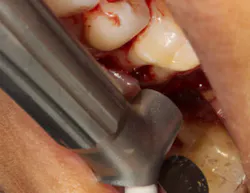

The advent of laser technology, either as an adjunct to surgical therapy or as a monotherapy, has been met with mixed results in the literature. (13) Recently, a new 9.3-micron CO2 laser (Solea from Convergent Dental) with the ability to cut both hard and soft tissue with efficiency was introduced to the dental market. This laser can penetrate deep defects with enough power to both thoroughly detoxify root surfaces and remove fibrous tissue, enhancing tissue repair (figure 2). (14) The spot size of the focal laser beam can also be controlled to a range of .25 mm to 1.25 mm so that the beam can be directed into furcation entrances. This allows previously difficult furcal defects to be detoxified prior to regenerative therapy. Because of this enhanced ability to detoxify, this laser has been able to change the prognosis of once-hopeless teeth (figure 3) and allow for tissue regeneration (figure 4) instead of extraction.

Figure 2: Solea laser with a beam size of .5 mm used to detoxify furcation. This beam can penetrate deep into the furcation.